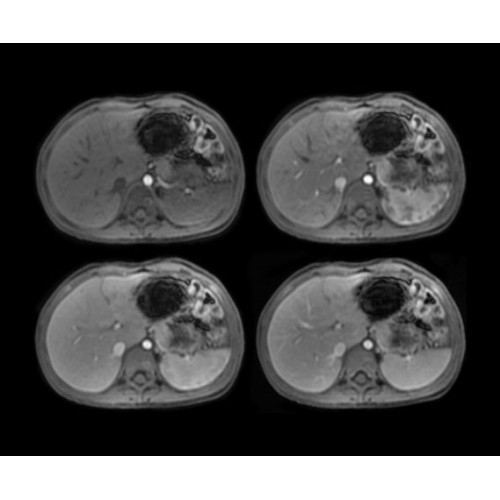

• OncoWorks — клинические приложения для обработки и визуализации анатомических и морфологических данных, специфичных для каждого типа онкологических образований.